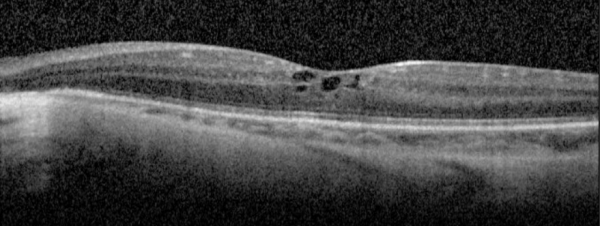

Optical Coherence Tomography

The IS/OS junction is typically preserved in the regions where autofluorescence signal is normal or increased. In the periphery, extensive loss of IS/OS junction, RPE and inner choroid reflectivity, accompanied by significant thinning of both inner and outer retina are often observed concurrently.

Cystoid macular edema is frequent, presumed to be due to impairment of the blood-retinal barrier. The largest case series with SD-OCT imaging showed all 7 (100%) patients were found to have multiple intraretinal cystoid changes and thickening of the fovea. [16] However, it is important to note whether there is petaloid leak at the macula in late phase of fundus fluorescein angiogram. In the presence of vertical tissue bridges, hyporeflective spaces in the retina on SD-OCT, the term foveschisis is used.[1] Macular hole[31] and epiretinal membrane are other possible macular involvement in the gyrate atrophy of the choroid and the retina.

Other findings in advanced disease can include deposits of retinal gliosis, outer retinal tubulation and choroidal neovascularization. [16][32][33]